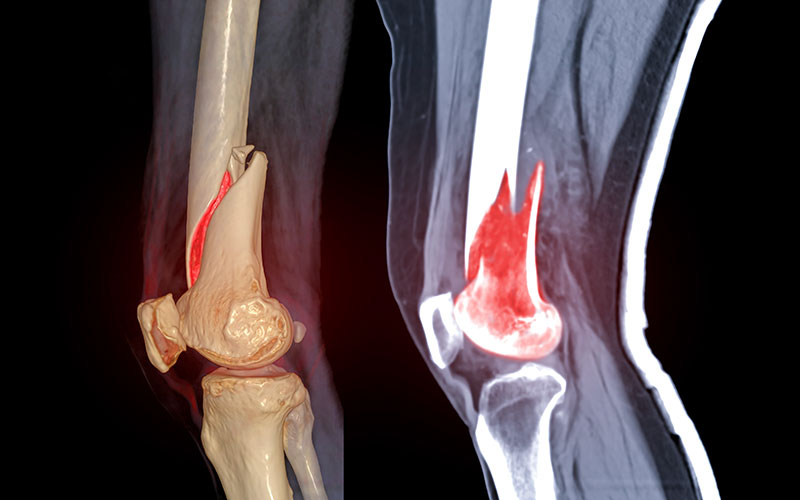

By partnering with LawFX, you gain access to CMI-certified medical illustrators who create visuals that are as beautiful as they are functional. Our goal is to simplify the complex and elevate communication.

The team at LawFX has worked with some of the top healthcare and pharmaceutical companies to visualize complex mechanisms of action. We ensure every piece we create is scientifically accurate and visually stunning.